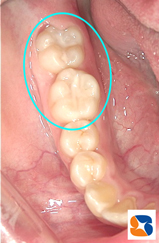

今回は、虫歯の予防についてのお話です。 写真の患者さんは、小学校5年生。永久歯の奥歯の溝が、茶色っぽく=写真左=なっていますね。 このままでは将来、虫歯になりそうで心配です。このような時、溝の中に材料名「シーラント」=写真右=を流し込み、青い光で固めます。歯を削らずに、そのままシーラントで溝を埋めるだけで虫歯の予防となります。あくまでも”予防”ですので、しっかり歯磨きは毎日、時間をかけておこなって下さいね。